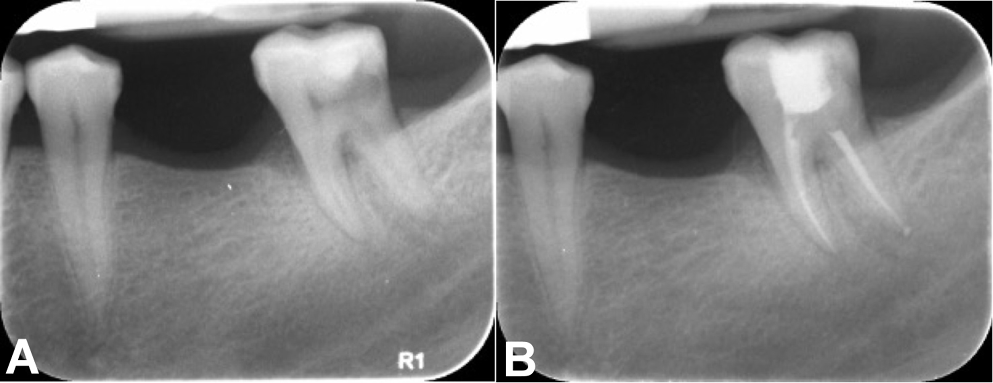

Group I: cold lateral compaction

After root canal debridement, the master cone was verified with an intraoral periapical radiograph. Once the working length was confirmed, the premixed injectable Cerafill RCS® sealer (Prevest DenPro Ltd.) was dispensed onto a paper mixing pad. The master cone (Dentsply Maillefer) was adequately coated with the sealer and placed into the canal at working length. Spreaders of an appropriate size were introduced 1 mm short of the working length to create lateral space for accessory cones. Accessory cones (Dentsply Maillefer) were then coated with the sealer and packed until the spreader penetrated no more than 1–2 mm into the root canal orifice. Before the excision of the accessory cones, an intraoral periapical radiograph was taken to confirm the quality of the seal. If any voids or spaces were detected, additional accessory cones were placed until an adequate seal was obtained. Finally, excess gutta-percha was removed using a heated plugger to 1 mm below the orifice level and condensed (Figure 2).